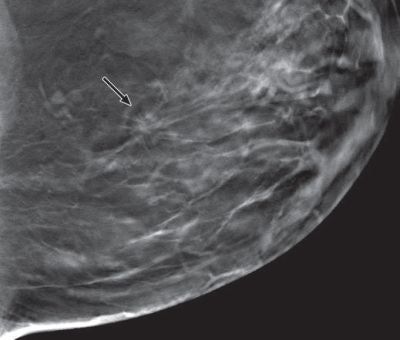

Comparison of digital mammography and tomosynthesis images in 42-year-old woman with 10-mm invasive ductal carcinoma in left breast. Craniocaudal images for digital mammography (above) and tomosynthesis (below). All clinical images courtesy of AJR.

Mediolateral oblique images for digital mammography (left) and tomosynthesis (right). All tomosynthesis images show improved visibility of cancer (arrow) and cancer margins compared with digital mammography.Addressing 'harms'